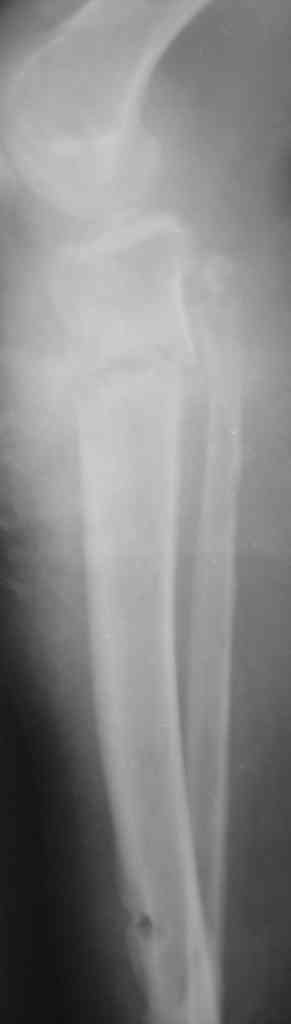

Патологический перелом голени, остеомиелит |

Женщина 30 лет,инвалид 1-й группы по рассеяному энцефаломиелиту (клинически нижний парапарез). В январе 2008 года получила закрытый винтообразный перелом большеберцовой кости в н/з и шейки малоберцовой кости со смещением отломков.

После травмы развились обширные эпидермальные пузыри голени и голеностопного сустава. После заживления ран произведено наложение аппарата Илизарова. П/о период без особенностей, больная поставлена на ноги (с ходьбой, естественно, проблемы). Наблюдалась на дому. Спустя месяц после операции отмечалось воспаление м/тканей области спиц проксимального базового кольца аппарата, отек в/з голени (больная передвигалась по дому на четвереньках!).Пришлось поменять кольцо на больший диаметр.Воспаление купировали. К концу второго месяца фиксации воспаление в области верхних спиц опять возникло, отделяемое сукровично-гнойное, незначительное. Проводилось местное лечение, отмечался умеренный отек голени в в/з, болезненность, гиперемии не было. Через три месяца после операции - клиническая проба, перелом сросся. Аппарат демонтирован. Спустя 4-5 дней после демонтажа отмечалась гипертермия до 39 в вечернее время. Раны кроме верхних зажили без проблем, верхние - в прежнем состоянии (незначительное серозное отделяемое).Проводилась АБТ, туалет ран, дренирование. Спустя 2 недели после снятия аппарата мать больной отметила появление подвижности в области коленного сустава. При осмотре - деформация голени в в/з (на уровне верхних спиц), подвижность на протяжении в/з, болезненность. Отек умеренный в в/з, гиперемии нет, гипертермия локальная умеренная.Коленный сустав отечен, жидкости нет. Сделали снимки (в приложении) - вот какая картина Больную госпитализировали - гипсовая лонгета, противовоспалительная терапия, взяли посев из ран. В анализах -лейкоциты до 8 тыс, сдвига формулы нет, СОЭ 42, но больная проходит курсы лечения бетафероном по РЭМ.